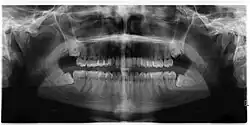

Impacted wisdom teeth are classified by their direction of impaction, their depth compared to the biting surface of adjacent teeth and the amount of the tooth's crown that extends through gum tissue or bone. Impacted wisdom teeth can also be classified by the presence or absence of symptoms and disease. Screening for the presence of wisdom teeth often begins in late adolescence when a partially developed tooth may become impacted. Screening commonly includes a clinical examination as well as x-rays such as panoramic radiographs.

If the tooth cannot be assessed with clinical exam alone, the diagnosis is made using either a panoramic radiograph or cone-beam CT. Where unerupted wisdom teeth still have eruption potential several predictors are used to determine the chance of the teeth becoming impacted. The ratio of space between the tooth crown length and the amount of space available, the angle of the teeth compared to the other teeth are the two most commonly used predictors, with the space ratio being the most accurate. Despite the capacity for movement into early adulthood, the likelihood that the tooth will become impacted can be predicted when the ratio of space available to the length of the crown of the tooth is under 1.[5]: 141